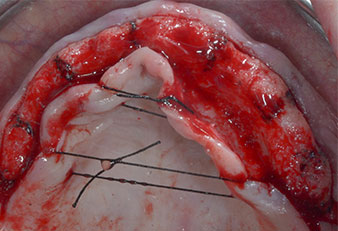

Поради сравнително твърдата кост (D2) в тази област, 10-милиметровото имплантно ложе в позиции 11 и 21 беше завършено с ротационен дрил с диаметър 4 mm в комбинация с W&H хирургичен обратен наконечник WS-75 L, W&H имплантологичен мотор Implantmed и опционалния W&H Osstell ISQ модул. За разлика от това, благодарение на меката кост, дисталните зони се подготвят до окончателен диаметър 3 mm, използвайки накрайник за Piezomed I3P. Имплантите най-накрая са поставени трансгингивално, за да остеоинтегрират за три месеца (Фиг. 6-10). Съществуващата протеза се фиксира на четирите временни импланта (Фиг. 8).

10-милиметров имплант на нивото на меките тъкани

Фиг. 6 10-милиметров имплант на нивото на меките тъкани е поставен на позиция 21. Имплантът в позиция 11 и трите леви дистални 4-милиметрови импланта са вече на мястото си.

Фиг. 7 Стабилността на импланта е установена със SmartPeg и W&H Osstell ISQ модул. Стойностите са в средния към високия диапазон с минимум ISQ 69.

Фиг. 8 След фиксиране на гингиво оформителите временните импланти се поставят в позиции 18, 12, 22 и 28.